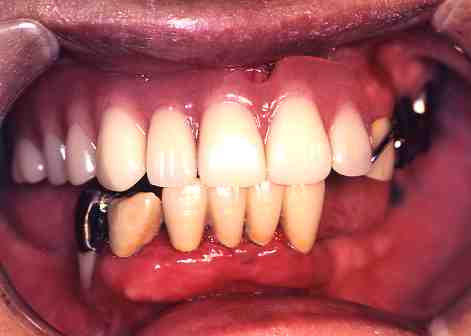

1.術前

下の歯のまわりの

歯ぐきが腫れています。